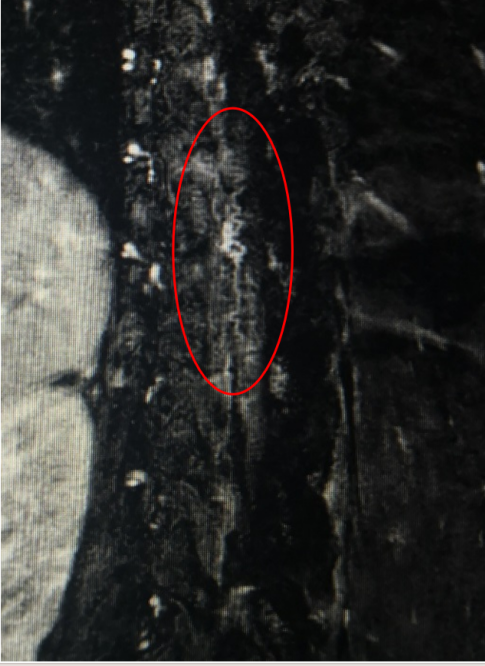

儿童下腰瘫,脊髓减压,脑脊液置换